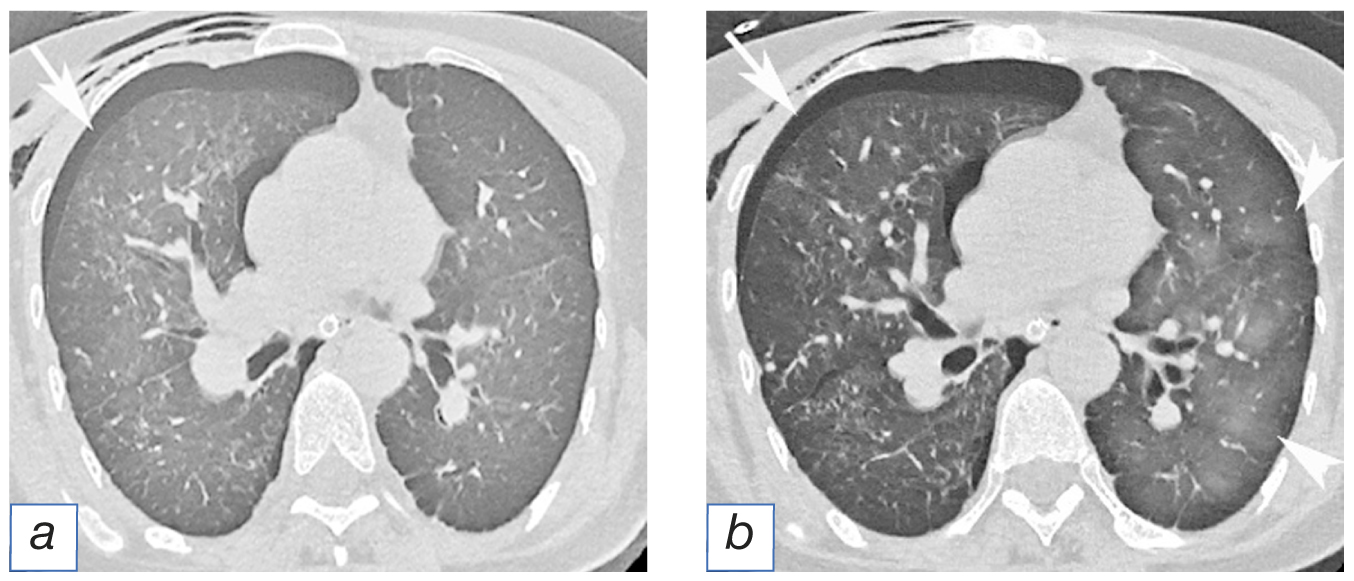

Laboratory and instrumental diagnostics. The initial assessment has revealed tachypnea (respiratory rate— 39 per minute), tachycardia (heart rate 115 per minute) with the blood pressure levels of 110/70 mm Hg along with the blood oxygen saturation (SpO2) levels being 93%. The parameters of the clinical hematology and biochemistry panels were within the reference ranges. Upon the radiography of the chest cavity organs: status post resection of segmentsI–II of the left lung, signs of massive spontaneous pneumothorax on the right side (Fig. 3).

Therapy. Thoracostomy was performed with further draining of 1500 cm3 of air. Upon the control computed tomography, the findings included an incomplete expansion of the right lung and emphysema in the soft tissues of the chest cavity (Fig. 4,а). The female patient has tolerated the procedure well and the symptoms of her pathological condition have decreased. The next morning, the patient had increased shortness of breath and her oxygen saturation (SpO2) has dropped to 86%. Upon the repeated computed tomography, multiple intralobular foci of decreased transparency were found in the left lung (ground glass-type) with gravity-related density gradients (see Fig. 4,б). Combined with the anamnestic data, this symptom has provided the possibility to come to the conclusion on the development of reexpansion edema, for the patient had no fever or leukocytosis, characteristic for pneumonia; there were no signs of aspiration or fluid overload, as well as signs of renal or cardiac failure.

Fig. 4. Female patient А., 53 years of age. Computed tomography image the thoracic cavity: а — air accumulation in the right pleural cavity (arrow), emphysema in the soft tissues in the anterior wall of the chest; b — air accumulation in the right pleural cavity (arrow), emphysema in the soft tissues in the anterior wall of the chest; decreased airness in the parenchyma of the left lung (ground glass-type), resulting due to reexpansion edema (point of arrow).

Diagnosis. The definitive diagnosis was stated as the following: “Reexpansion contralateral edema of the left lung, secondary in terms of pneumothorax in the right lung”.

Outcomes and prognosis. After proper oxygen therapy along with the administration of corticosteroid medications and draining of the pleural cavity (using the Bulau’s method), within 5 days the right lung has completely expanded without the development of ipsilateral reexpansion edema, while the reexpansion edema of the left lung has completely resolved.